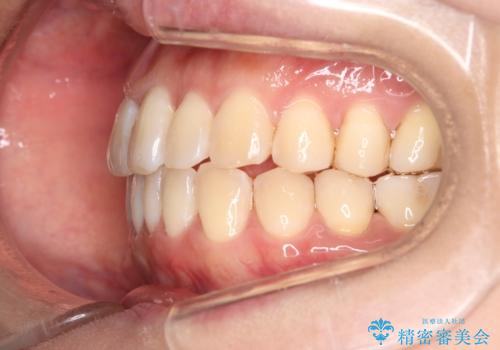

【インビザライン】前歯の捻れ気になる

- 上の前歯の捻れを主訴に来院されました。

前歯の捻れとがたつきを改善するために、IPR(歯と歯の間を削る処置)と歯列拡大をすることで歯並びを整えていく治療計画を立てました。

かみ合わせを整えるためにゴム掛けも行いながら、治療していきました。

患者様にマウスピースの使用とゴム掛けを頑張っていただいたおかげでリファイメント(マウスピースの再発注)も1回で終了することができました。